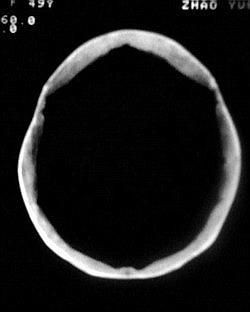

患者/49y/ 女/4年前有脑梗, 现因右侧肢体无力来院做ct扫描 ! 老师们看看这骨头有事吗?钙化点是什么原因呀??

1.颅骨对称性、形态规整性增厚,应属发育异常。四叠体池左后侧单发点状钙化,无其他阳性表现,多属正常,不需要过多关注。

2、颅骨形态规整性的增厚,密度增高,有无骨髓方面的疾病,建议骨髓穿刺。

可能为颅骨内板增生症,以额骨多见,常见于女性.多无临床意义.部分病人可有头痛.可找相关资料看看.

2.颅骨内外板广泛性增厚,板障狭窄甚至消失,双侧对称。无明显相应临床症状。考虑“泛发性骨皮质增厚症”。可进一步检查下颌骨及管状骨骨干。(下颌骨骨小梁增多、密集,密度增高亦为本病特点,管状骨骨干皮质向内增厚引起骨皮质厚度增加,骨密度增浓、髓腔狭窄但不消失,骨干周径较少增加)。与石骨症鉴别,后者很少影响颅盖骨和下颌骨,管状骨改变主要累及干骺端和骨骺,而骨干皮质较少增厚,椎体和髂骨翼有特征性表现。

“泛发性骨皮质增厚症,又称骨内膜增生症(endosteal hyperostosis):分为常染色体隐性遗传性疾病(van buchem)和常染色体显性遗传性骨硬化症(worth病)。后者更少见,亦较轻。两者的病理上均为骨内膜 成熟的板状新生骨形成,髓腔变窄。颅骨、颅底骨 、下颌骨,肋骨、四肢骨及骨盆骨、脊柱均可见骨内膜增生,髓腔变窄或消失,但骨外径不加大,骨骺不累及。”

本例的确应该这个病。建议楼主检查病人其他部位有无类似表现,以便确诊。